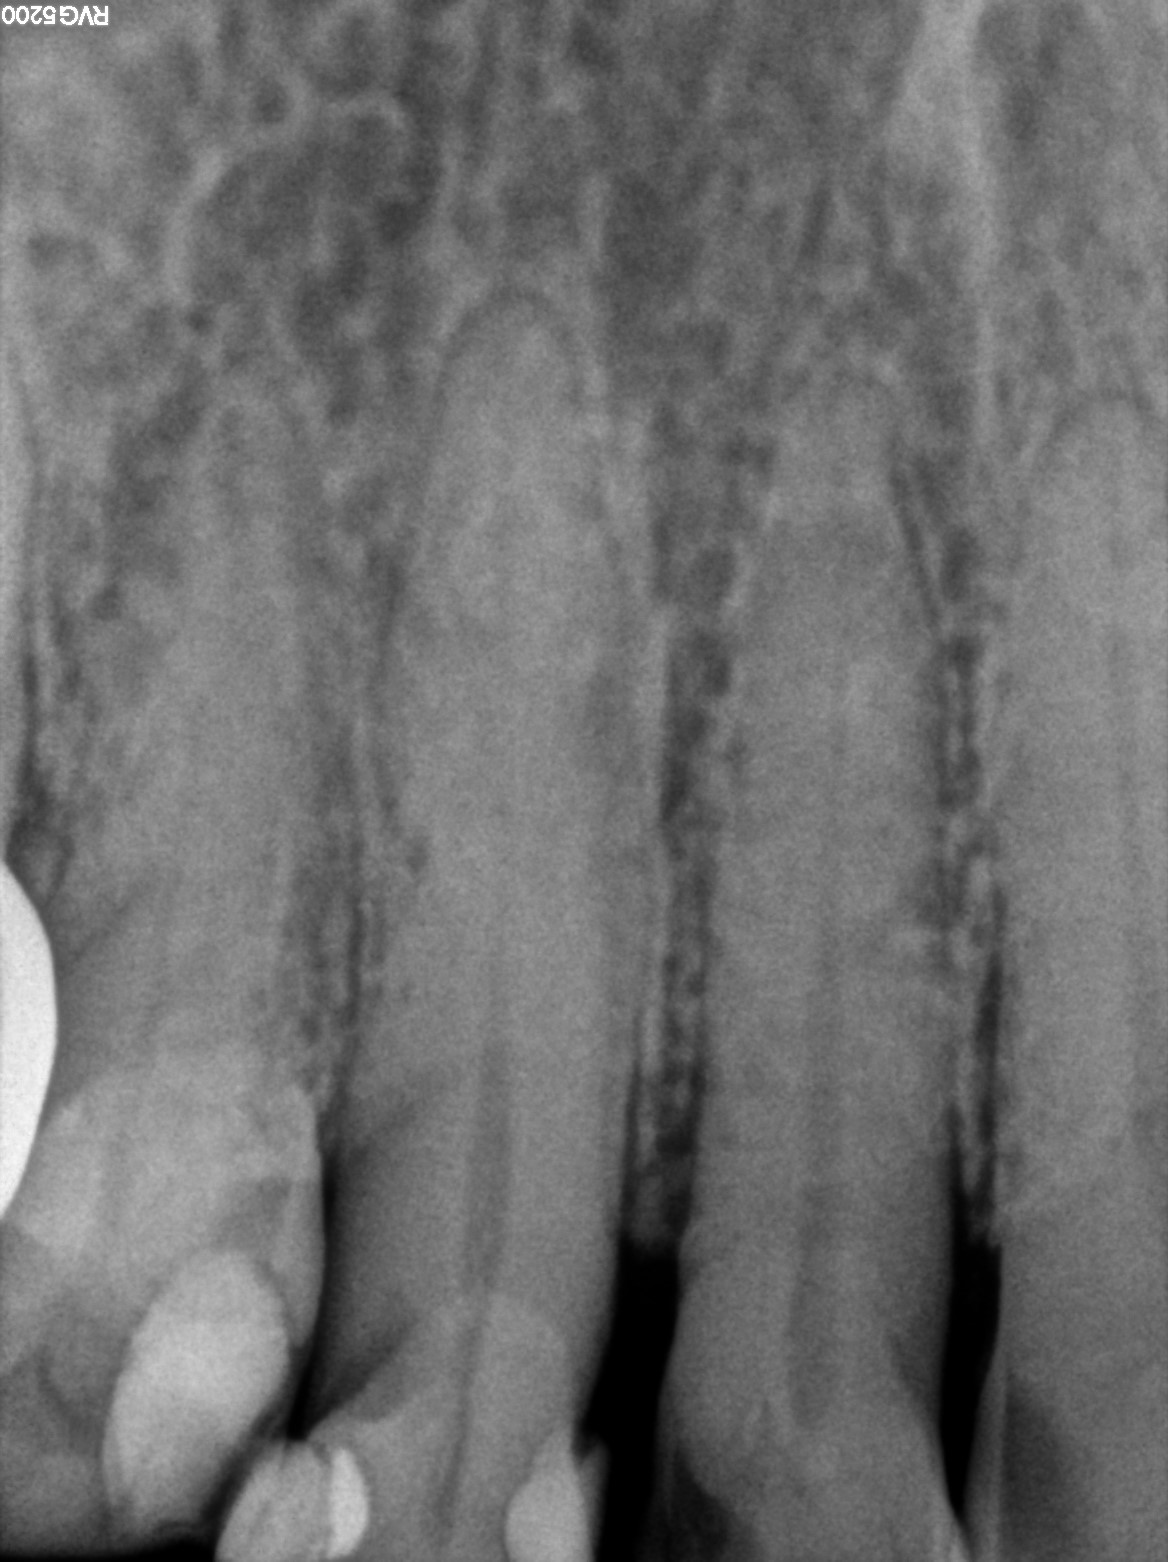

Dental Radiographs FHIR: DocumentReference · LOINC 24641-7

xray_1772525715_0.jpg

24641-7